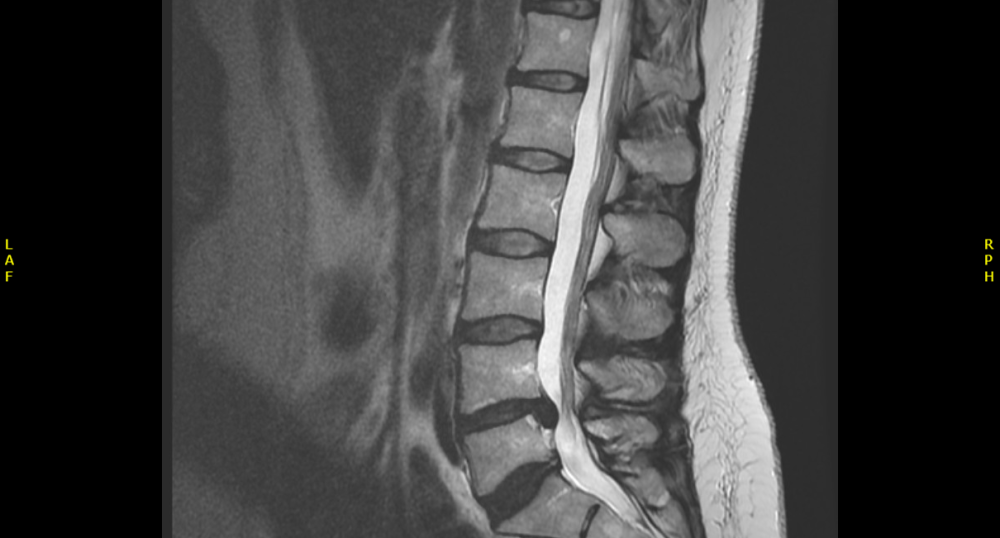

- A 35 year old lady presented with severe onset back and bilateral radicular leg pain, left leg worse affected than the right. She also reported urgency of micturition and some weakness of the left leg. On examination she had signs suggestive of a lumbar disc prolapse.

- She went on to have an MRI scan of the lumbar spine

- Label the MRI scan, pointing out abnormalities

What can you see in this scan done seven months post spinal surgery?

- Is there a recurrent disc prolapse?

- Can you see any post operative relevant changes?

- Is there any other pathology?